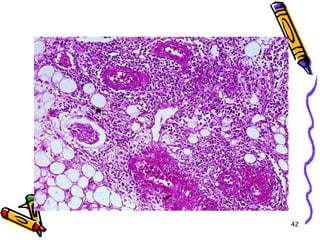

POLİARTERİTİS

• PAN, küçük ve orta büyüklükteki arterlerin

transmural nekrotik iltihabı ile giden

sistemik bir vaskülit

• Özellikle muskuler arterlerin dallanma

noktalarını tutar

• Tutulum, fokal, dağınık ve epizodik

• Lezyonların yaşı değişken

• Genç erişkin hastalığı

Mikroskopi

• Lezyonlar keskin sınırlı ve segmentaldir

• Fibrinoid nekrozla birlikte lökositik

inflamasyon ve tromboz

• İnflamasyon nedeni ile duvarda zayıflama

ve anevrizmal dilatasyon

• Damarın beslediği dokularda infarktüs,

atrofi, hemoraji